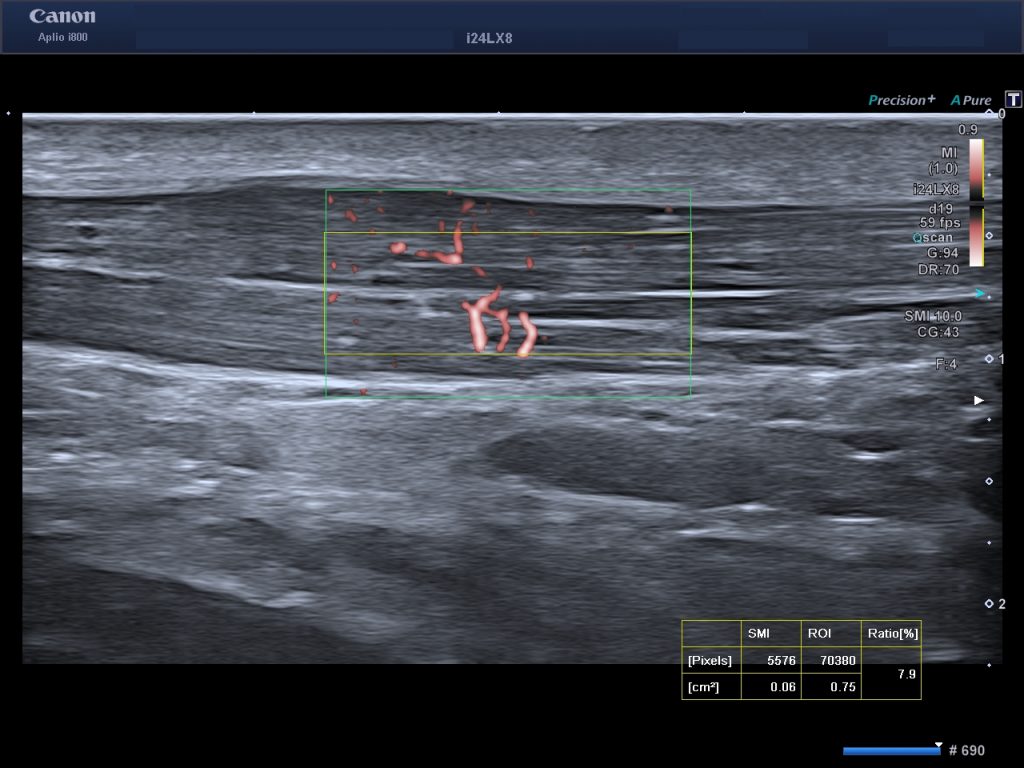

Professor Knobloch führt seit 2005 ultraschall-navigierte Sklerosierungen von Neogefäßen als Spezialtherapie bei Sehnenerkrankungen durch und ist Ultraspezialist für diese Therapieform.

In der SportPraxis Austria in Perchtoldsdorf bei Wien setzen wir ultraschall-navigierte gezielte Injektionstherapien ein, um Schmerzen zu lindern und Heilungsprozesse zu unterstützen. Durch präzise navigierte Spritzen – etwa bei der Sklerosierung von Neogefäßen bei Sehnenerkrankungen oder regenerativer Hyaluronsäuren – können wir direkt am Ort des Geschehens wirken. Ob ein gereiztes Kniegelenk bei Arthrose, ein entzündeter Tennisellenbogen oder hartnäckige Achillessehnenbeschwerden: Ultraschall-navigierte Injektionen bieten eine schnelle und effektive Linderung für Hobby- wie Profisportler und auch für aktive Senior:innen in der Hand eines erfahrenen Anwenders.

Gezielte ultraschall-navigierte Injektionsbehandlungen kommen insbesondere bei hartnäckigen Sehnenproblemen wie auch als Eskalationsmaßnahme bei Arthrosen in der SportPraxis Austria in Frage, besonders wenn weitere konservative Maßnahmen (Physiotherapie, energie-basierte Therapien) allein nicht ausreichen. Typische Patientengruppen, die von Injektionstherapien profitieren, sind: